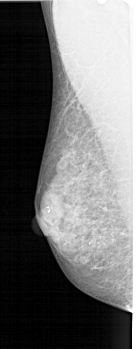

A_1517_1.LEFT_MLO

LEFT_MLO LINES 4876 PIXELS_PER_LINE 1891 BITS_PER_PIXEL 12 RESOLUTION 43.5 NON_OVERLAY